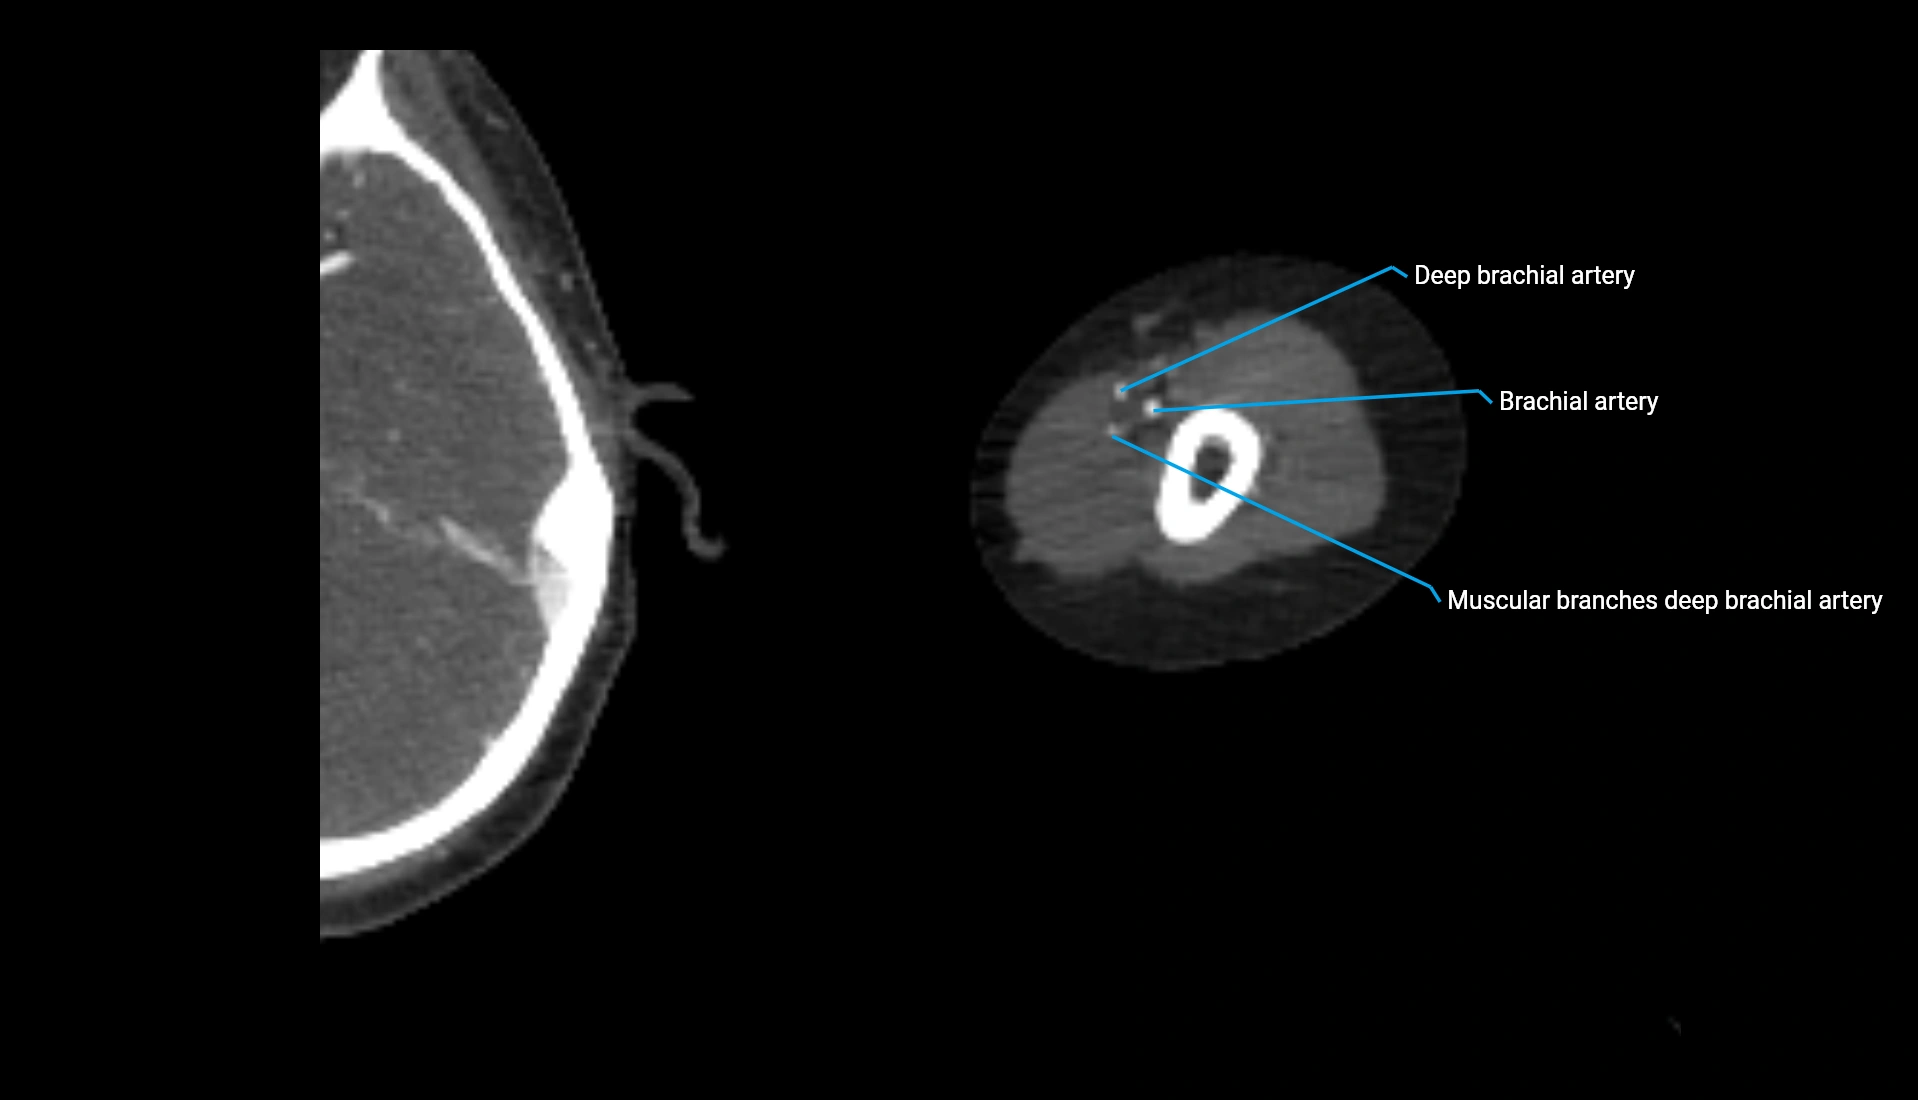

CT Appearance

Non-Contrast CT:

• Cortex: High-density, sharply defined

• Subchondral bone: Dense cancellous matrix

• Articular surface: Smooth concave contour articulating with the capitellum

• Excellent for evaluating bone integrity, alignment, and subtle fractures

Post-Contrast CT:

• Bone: No enhancement

• Joint capsule and synovium: Mild enhancement outlining the joint

• Improves contrast between soft tissues and bony margins

• Useful in detecting subtle joint abnormalities or postoperative changes